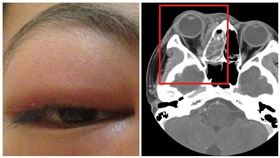

腫成金魚眼 長期鼻塞釀蜂窩性組織炎

小心鼻子過敏太嚴重,可能引發鼻竇炎,甚至蜂窩性組織炎...